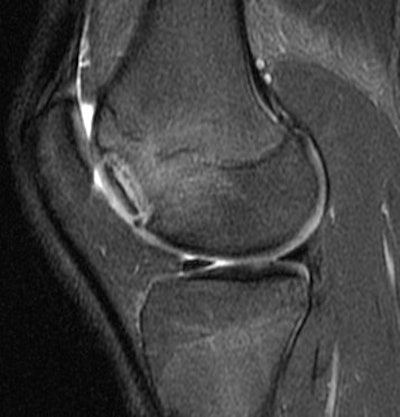

|  |

| Sagittal MRI of JOCD on 1.5-tesla scanner. Protocol included FSE and T2-weighted imaging (TR/TE 3500/55). Image courtesy of Dr. Nancy Major, Duke University Medical Center, Durham, NC. |